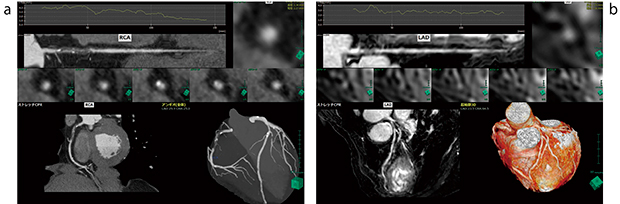

画像のノイズ成分,狭窄病変における画素値の不連続性などの影響を受けない高精度なセグメンテーションを行えるため,短時間で処理でき,かつユーザー間において画像作成結果の差異を生じない画像を提供できる(図1)。

図1 CT,MR画像から自動で心臓,冠動脈を抽出した画像例

a:RCA #1 Subtotal Occlusion。高度狭窄を有する冠動脈CT画像。

b:LAD #6 Stenosis。狭窄を有する冠動脈MR画像。